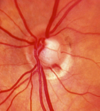

- Fundo de olho: Neuropatia óptica glaucomatosa

- Retinografia: Registro anatômico utilizado para documentação.

Quais as características são mais comuns no GPN do que no GPAA?

Hemorragia peripapilar (mais comuns na porção temporal inferior do disco).

Atrofia Zona-beta.

Escavações mais planas.

Fosseta adquirida (mais comuns na porção temporal inferior do disco).